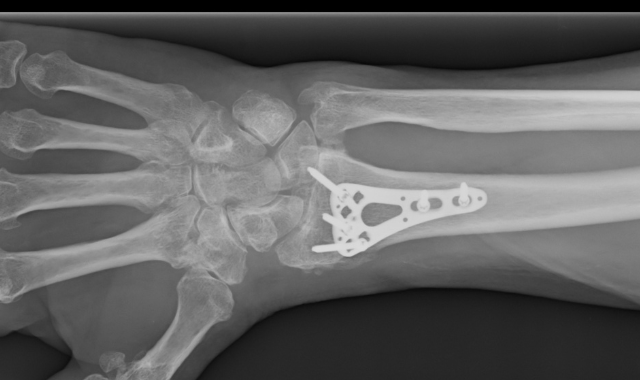

Texas Orthopedics provides comprehensive orthopedic care by offering on-site X-ray, MRIs, bone density scans, physical and occupational therapy, general orthopedic services, sports medicine, spine care, joint replacement, fracture and trauma care, infusion therapy, and a Joint Commission-accredited outpatient surgery center. In addition to orthopedic surgeons, we have physical medicine and rehabilitation specialists at our locations in Kyle, Round Rock, Lakeway, Northwest Austin, Leander, Central Austin, and South Austin, TX.